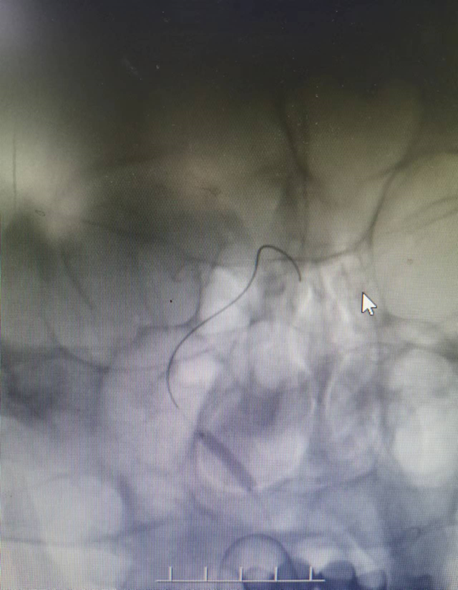

入院影像检查

导丝怎么扩【载药时代 球扩天下】NOVA DES®颅内药物洗脱支架在症状性颅内动脉狭窄中的应用—烟台鲁东医院使用体会二例!_https://www.jmylbn.com_新闻资讯_第4张

RVI

RICA

导丝怎么扩【载药时代 球扩天下】NOVA DES®颅内药物洗脱支架在症状性颅内动脉狭窄中的应用—烟台鲁东医院使用体会二例!_https://www.jmylbn.com_新闻资讯_第5张

LICA

LVI

重要影像结论:双侧颈内动脉起始段轻度狭榨,左侧椎动脉V4段重度狭窄;左侧大脑后动脉颅内段闭塞。

导丝怎么扩【载药时代 球扩天下】NOVA DES®颅内药物洗脱支架在症状性颅内动脉狭窄中的应用—烟台鲁东医院使用体会二例!_https://www.jmylbn.com_新闻资讯_第6张

LVA狭窄90%

重要影像结论:左椎动脉V4重度狭窄,大于90%,右椎动脉纤细远端闭塞。